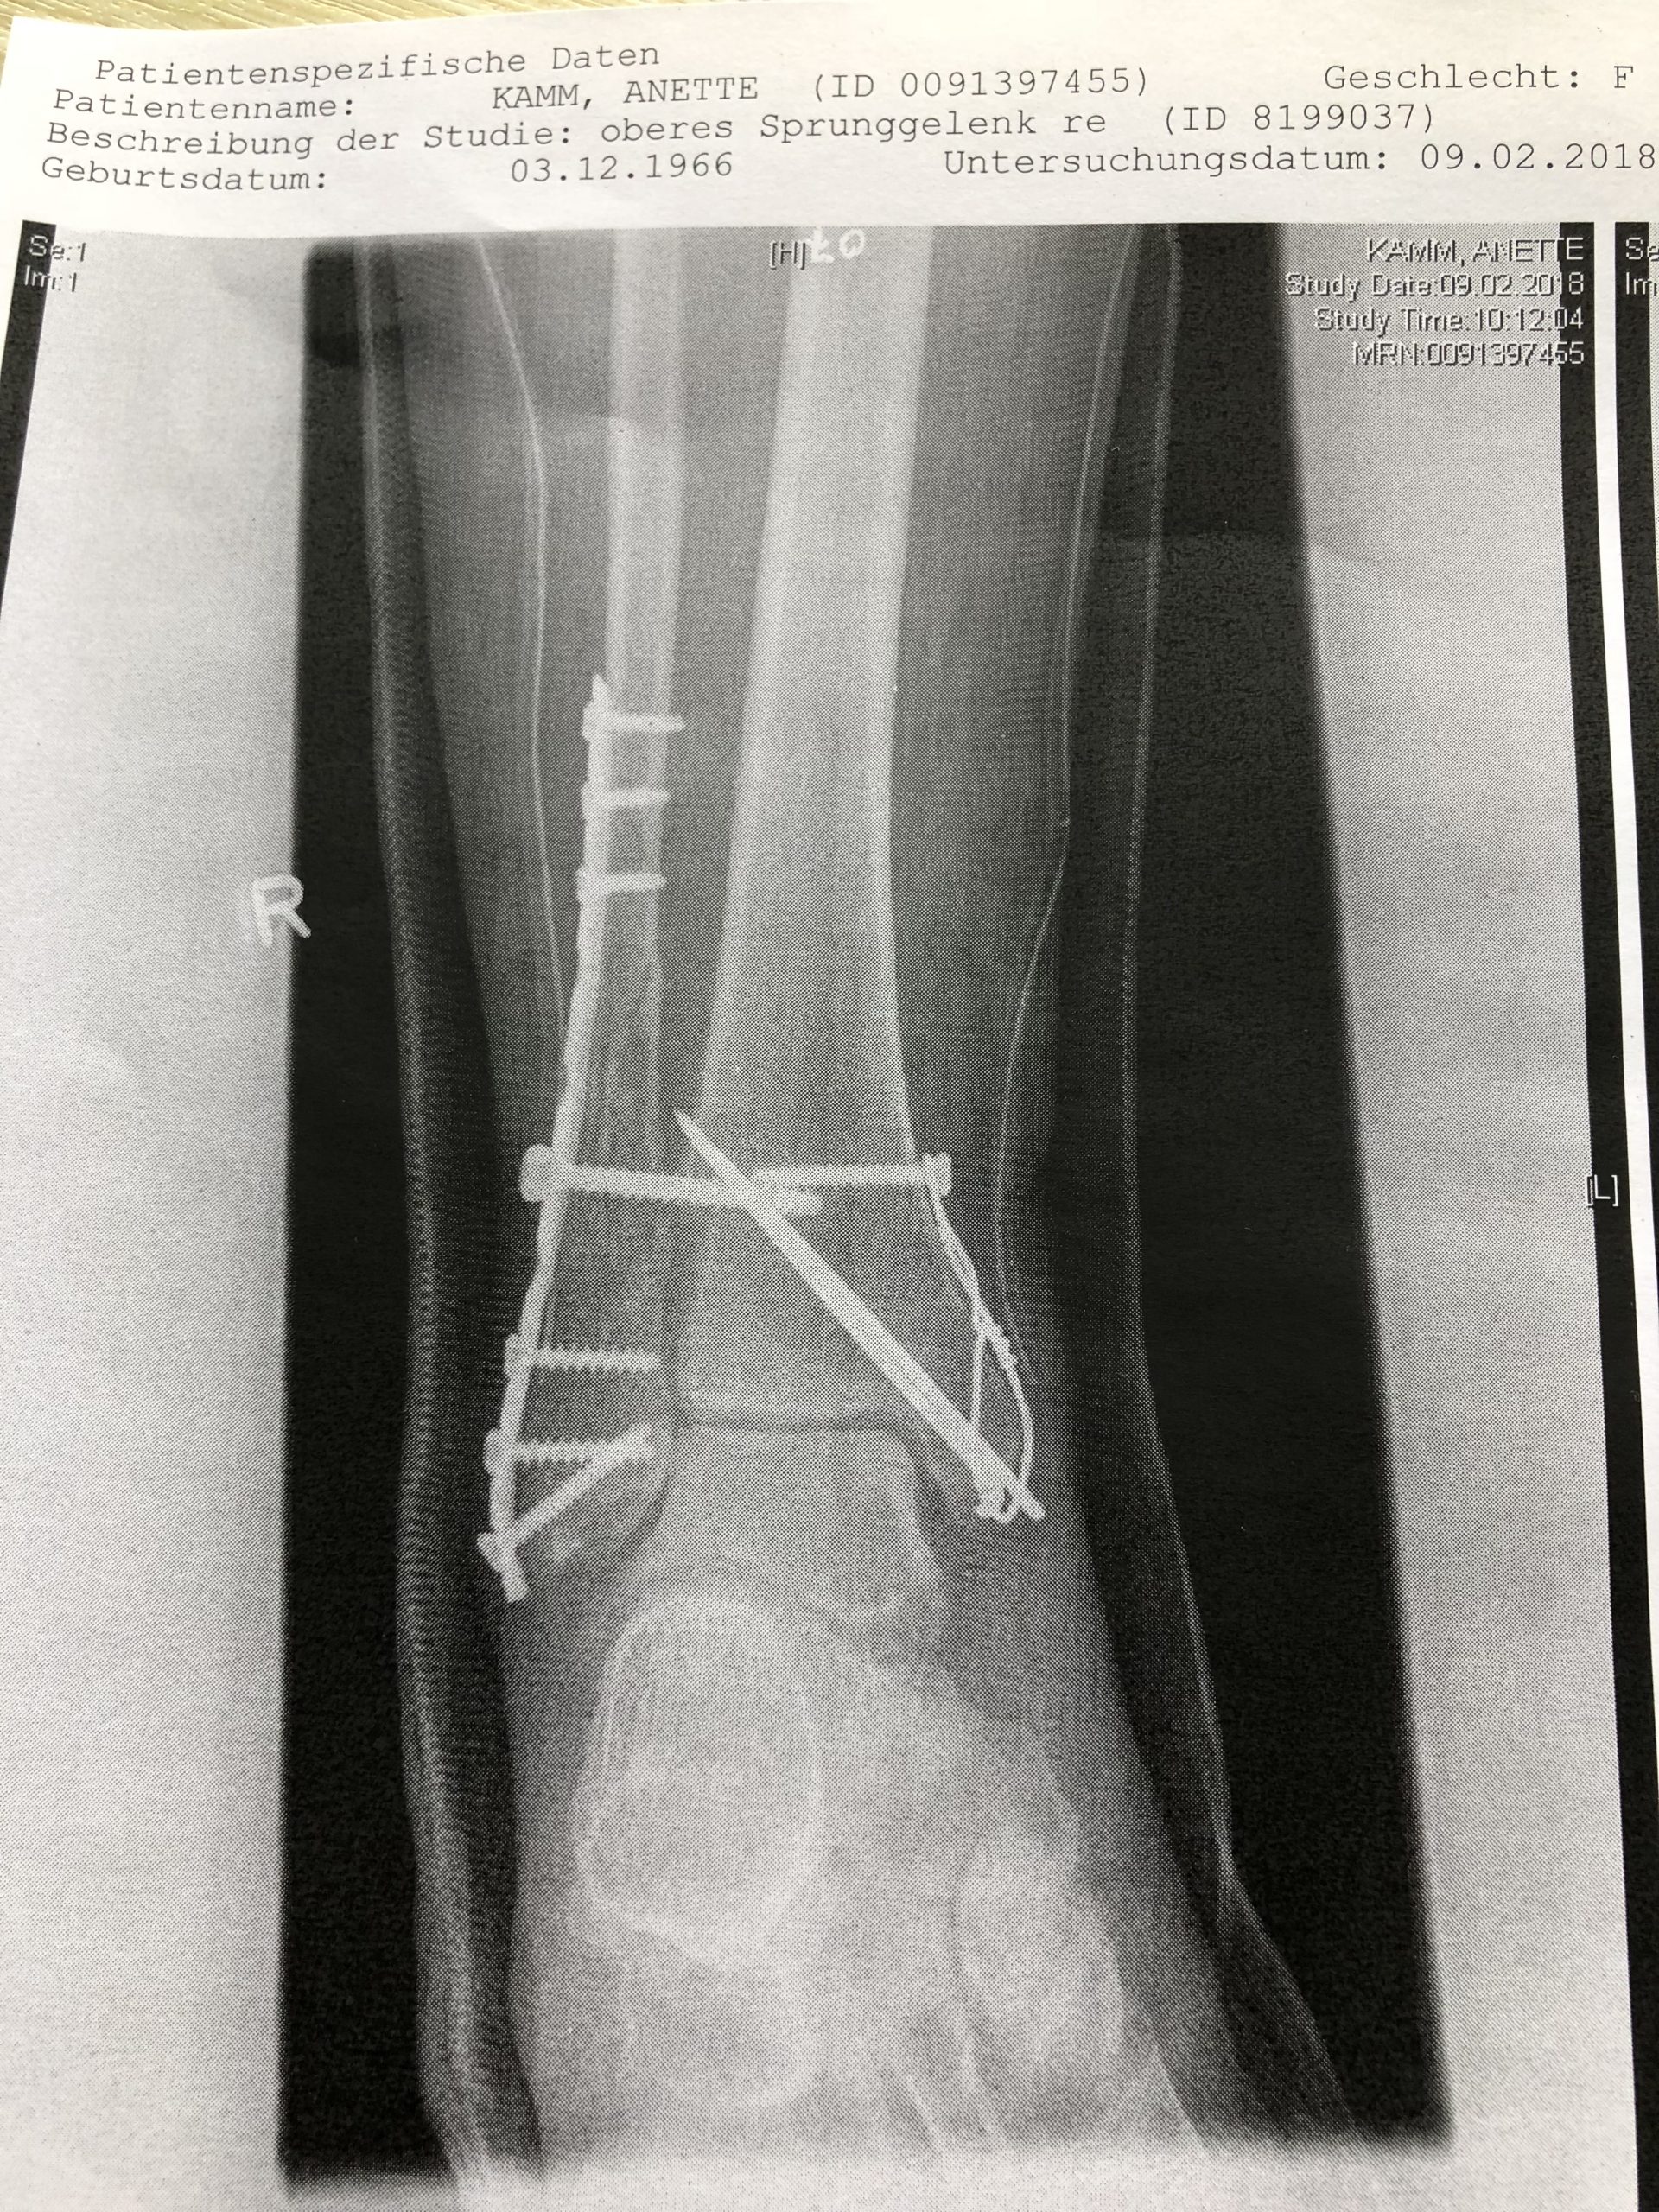

Für die Orthopäden unter uns gibt es noch mehr Details zu diesem besonderen Fall

Drähte, Leisten und Schrauben ... was man in so ein Bein alles einbauen kann, damit es wieder richtig zusammen wächst